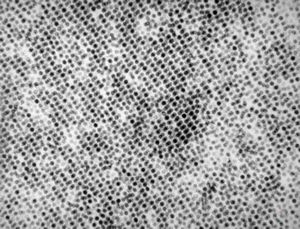

F, 24y. | molluscum contagiosum … virions

F, 24y. | molluscum contagiosum

F, 7y. | molluscum contagiosum … virions